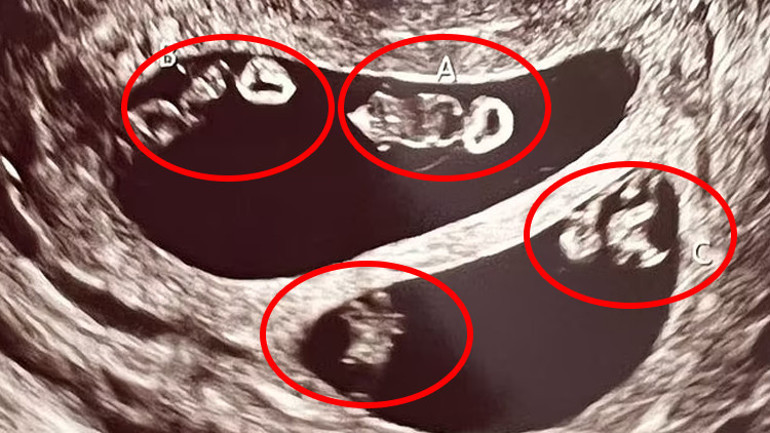

Daha önceki ilişkisinden de bir kızı olan anne adayı karnındaki dört bebeğin dördüz değil iki ayrı tek yumurta ikizi olduğunu öğrendi.

Bu keşfin ultrason teknisyenini bile şoke ettiğini anlatan anne adayı, "Taramayı ilk başlattığı zaman ekrana baktı ve 'A,B' yazdı. Durup bir an ona baktım. Görünen o ki ikizlerim olacaktı." diye sözlerine başladı ve şöyle devam etti;

"Teknisyenin kafasının karıştığını görebiliyordum. Ekranda gördüğü şeyin gerçek olup olmadığını anlamak için odadan çıkmak zorunda kaldı. Döndüğünde ise bana inanılmaz durumu anlattı. Dört bebeğe hamileydim. İki kız ve iki erkek."